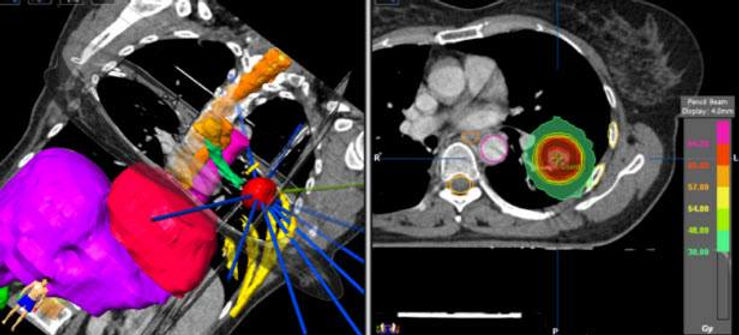

In radiotherapy, radiation treatment planning is the process in which a team consisting of radiation oncologists, radiation therapists, medical physicists and medical dosimetrists PLAN the appropriate external beam radiotherapy or internal brachytherapy treatment technique for a patient with cancer.

Intensity-modulated radiation therapy (IMRT) is an advanced type of radiation therapy used to treat cancer and also non-cancerous tumors. IMRT uses advanced technology to manipulate photon and proton beams of radiation to conform to the shape of a tumor.